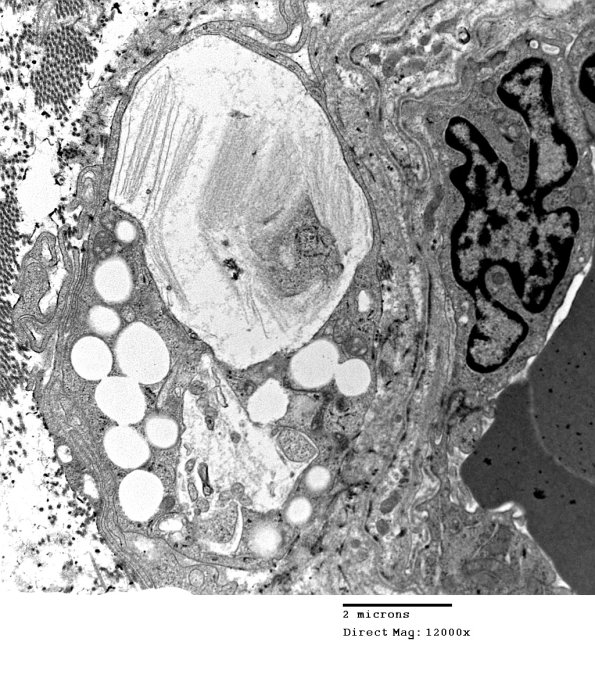

4H2 Axonal Degeneration (Case 10) 036 - Copy

A close-up of one of the macrophages seen in image #4H1.